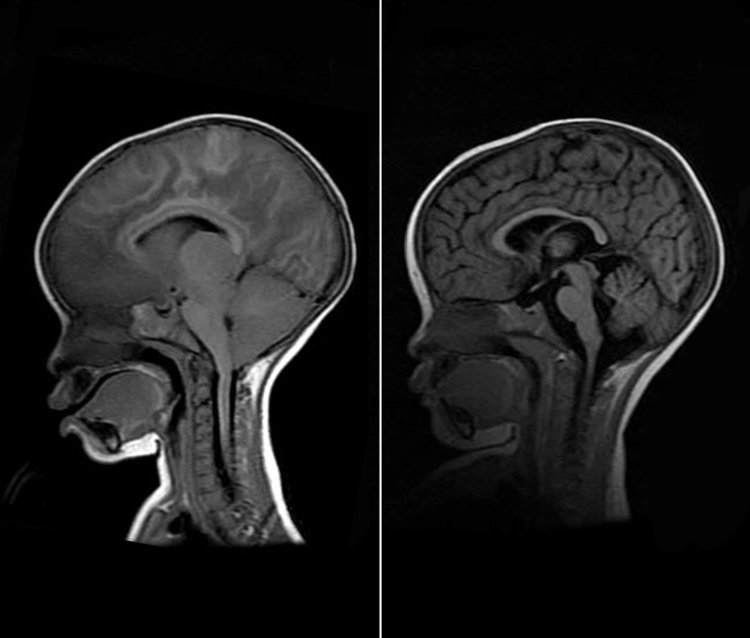

ଭୁବନେଶ୍ୱର: ମଶା, ମଣିଷର କିଭଳି ଅବସ୍ଥା କରିପାରେ, ଆପଣ ଚର୍ଚ୍ଚିତ ଫିଲ୍ମ ଦମନରେ ଦେଖିଥିବେ । ଲୋକଙ୍କୁ ରୋଗ ମୁକ୍ତ ରଖିବା ପାଇଁ ଜଣେ ଡାକ୍ତର କରିଥିବା ସଂଘର୍ଷକୁ ବି ବୁଝିଥିବେ । ଫିଲ୍ମର କାହାଣୀ ଭଳି ବାସ୍ତବ ଦୁନିଆରେ ବି ରୋଗର ମୁକାବିଲା ପାଇଁ ଏକ ଚମକ୍ରାର କରି ଦେଖାଇଛନ୍ତି ଭୁବନେଶ୍ୱର ଜୀବ ବିଜ୍ଞାନ ପ୍ରତିଷ୍ଠାନର ବୈଜ୍ଞାନିକ ଅରୁଣ ନାଗରାଜ ଏବଂ ତାଙ୍କ ଟିମ୍ । ବ୍ରେନ୍ ମେଲେରିଆ ବା ମସ୍ତିଷ୍କ ଜ୍ୱର ପାଇଁ ଓଡ଼ିଶାରୁ ବାହାରିଛି ଔଷଧ । ଏହି ଔଷଧକୁ ଜୀବଜନ୍ତୁଙ୍କ ଉପରେ ପରୀକ୍ଷଣ କରାଯାଇଛି । ଯାହା ଶତପ୍ରତିଶତ ସଫଳ ହୋଇଛି । ଖୁବ୍ ଶୀଘ୍ର ଏହାକୁ ମାନବ ପରୀକ୍ଷଣ କରାଯିବ ।

ଗର୍ଭବତୀ ଓ ୫ ବର୍ଷରୁ କମ୍ ଶିଶୁମାନେ ମ୍ୟାଲେରିଆ ରୋଗରେ ଆକ୍ରାନ୍ତ ହେବାର ଆଶଙ୍କା ଅଧିକ । ଏଭଳି ସ୍ଥିତିରେଏହି ଔଷଧ ମ୍ୟାଲେରିଆ ଓ ବ୍ରେନ୍ ମ୍ୟାଲେରିଆ ରୋଗୀଙ୍କ ପାଇଁ ବରଦାନ ହେବ । ଓଡ଼ିଶା ଭଳି ମ୍ୟାଲେରିଆ ପ୍ରବଣ ରାଜ୍ୟରେ ମହୌଷଧି ଭଳିି କାମ କରିବ । ୨୦୨୧ରେ ସାରାଦୁନିଆରେ ୨୪୭ ନିୟୁତ ଲୋକ ମ୍ୟାଲେରିଆରେ ଆକ୍ରାନ୍ତ ହୋଇଥିଲେ । ୬ ଲକ୍ଷ ୧୯ ହଜାର ଲୋକ ମ୍ୟାଲେରିଆରେ ମୃତ୍ୟୁବରଣ ହୋଇଥିଲା । ବଡ଼ କଥା ହେଉଛି, କେବଳ ମ୍ୟାଲେରିଆ ନୁହେଁ, ଆଇଏଲସ’ର ବୈଜ୍ଞାନିକମାନେ ଜନଜାତିଙ୍କୁ ହେଉଥିବା ରୋଗର ଚିହ୍ନଟ ଏବଂ ନିରାକରଣ ଉପରେ ମଧ୍ୟ ଗବେଷଣା ଜାରି ରଖିଛନ୍ତି ।